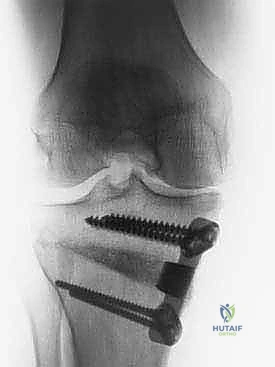

3. إجراء القطع العظمي (The Osteotomy):

باستخدام أدوات دقيقة ومناشير جراحية متطورة، يتم عمل قطع غير مكتمل في عظمة الساق. هناك طريقتان رئيسيتان:

* الشق المفتوح (Opening Wedge): يتم فتح العظم من الداخل وإضافة طعم عظمي (صناعي أو طبيعي) لملء الفراغ وتعديل الزاوية. وهي الطريقة الأكثر شيوعاً حالياً.

* الشق المغلق (Closing Wedge): يتم إزالة إسفين (مثلث) صغير من العظم من الجهة الخارجية وإغلاق الفراغ.

4. تعديل المحور:

يتم فتح العظم تدريجياً وببطء شديد حتى الوصول إلى الزاوية التي تم حسابها في التخطيط الرقمي قبل الجراحة.